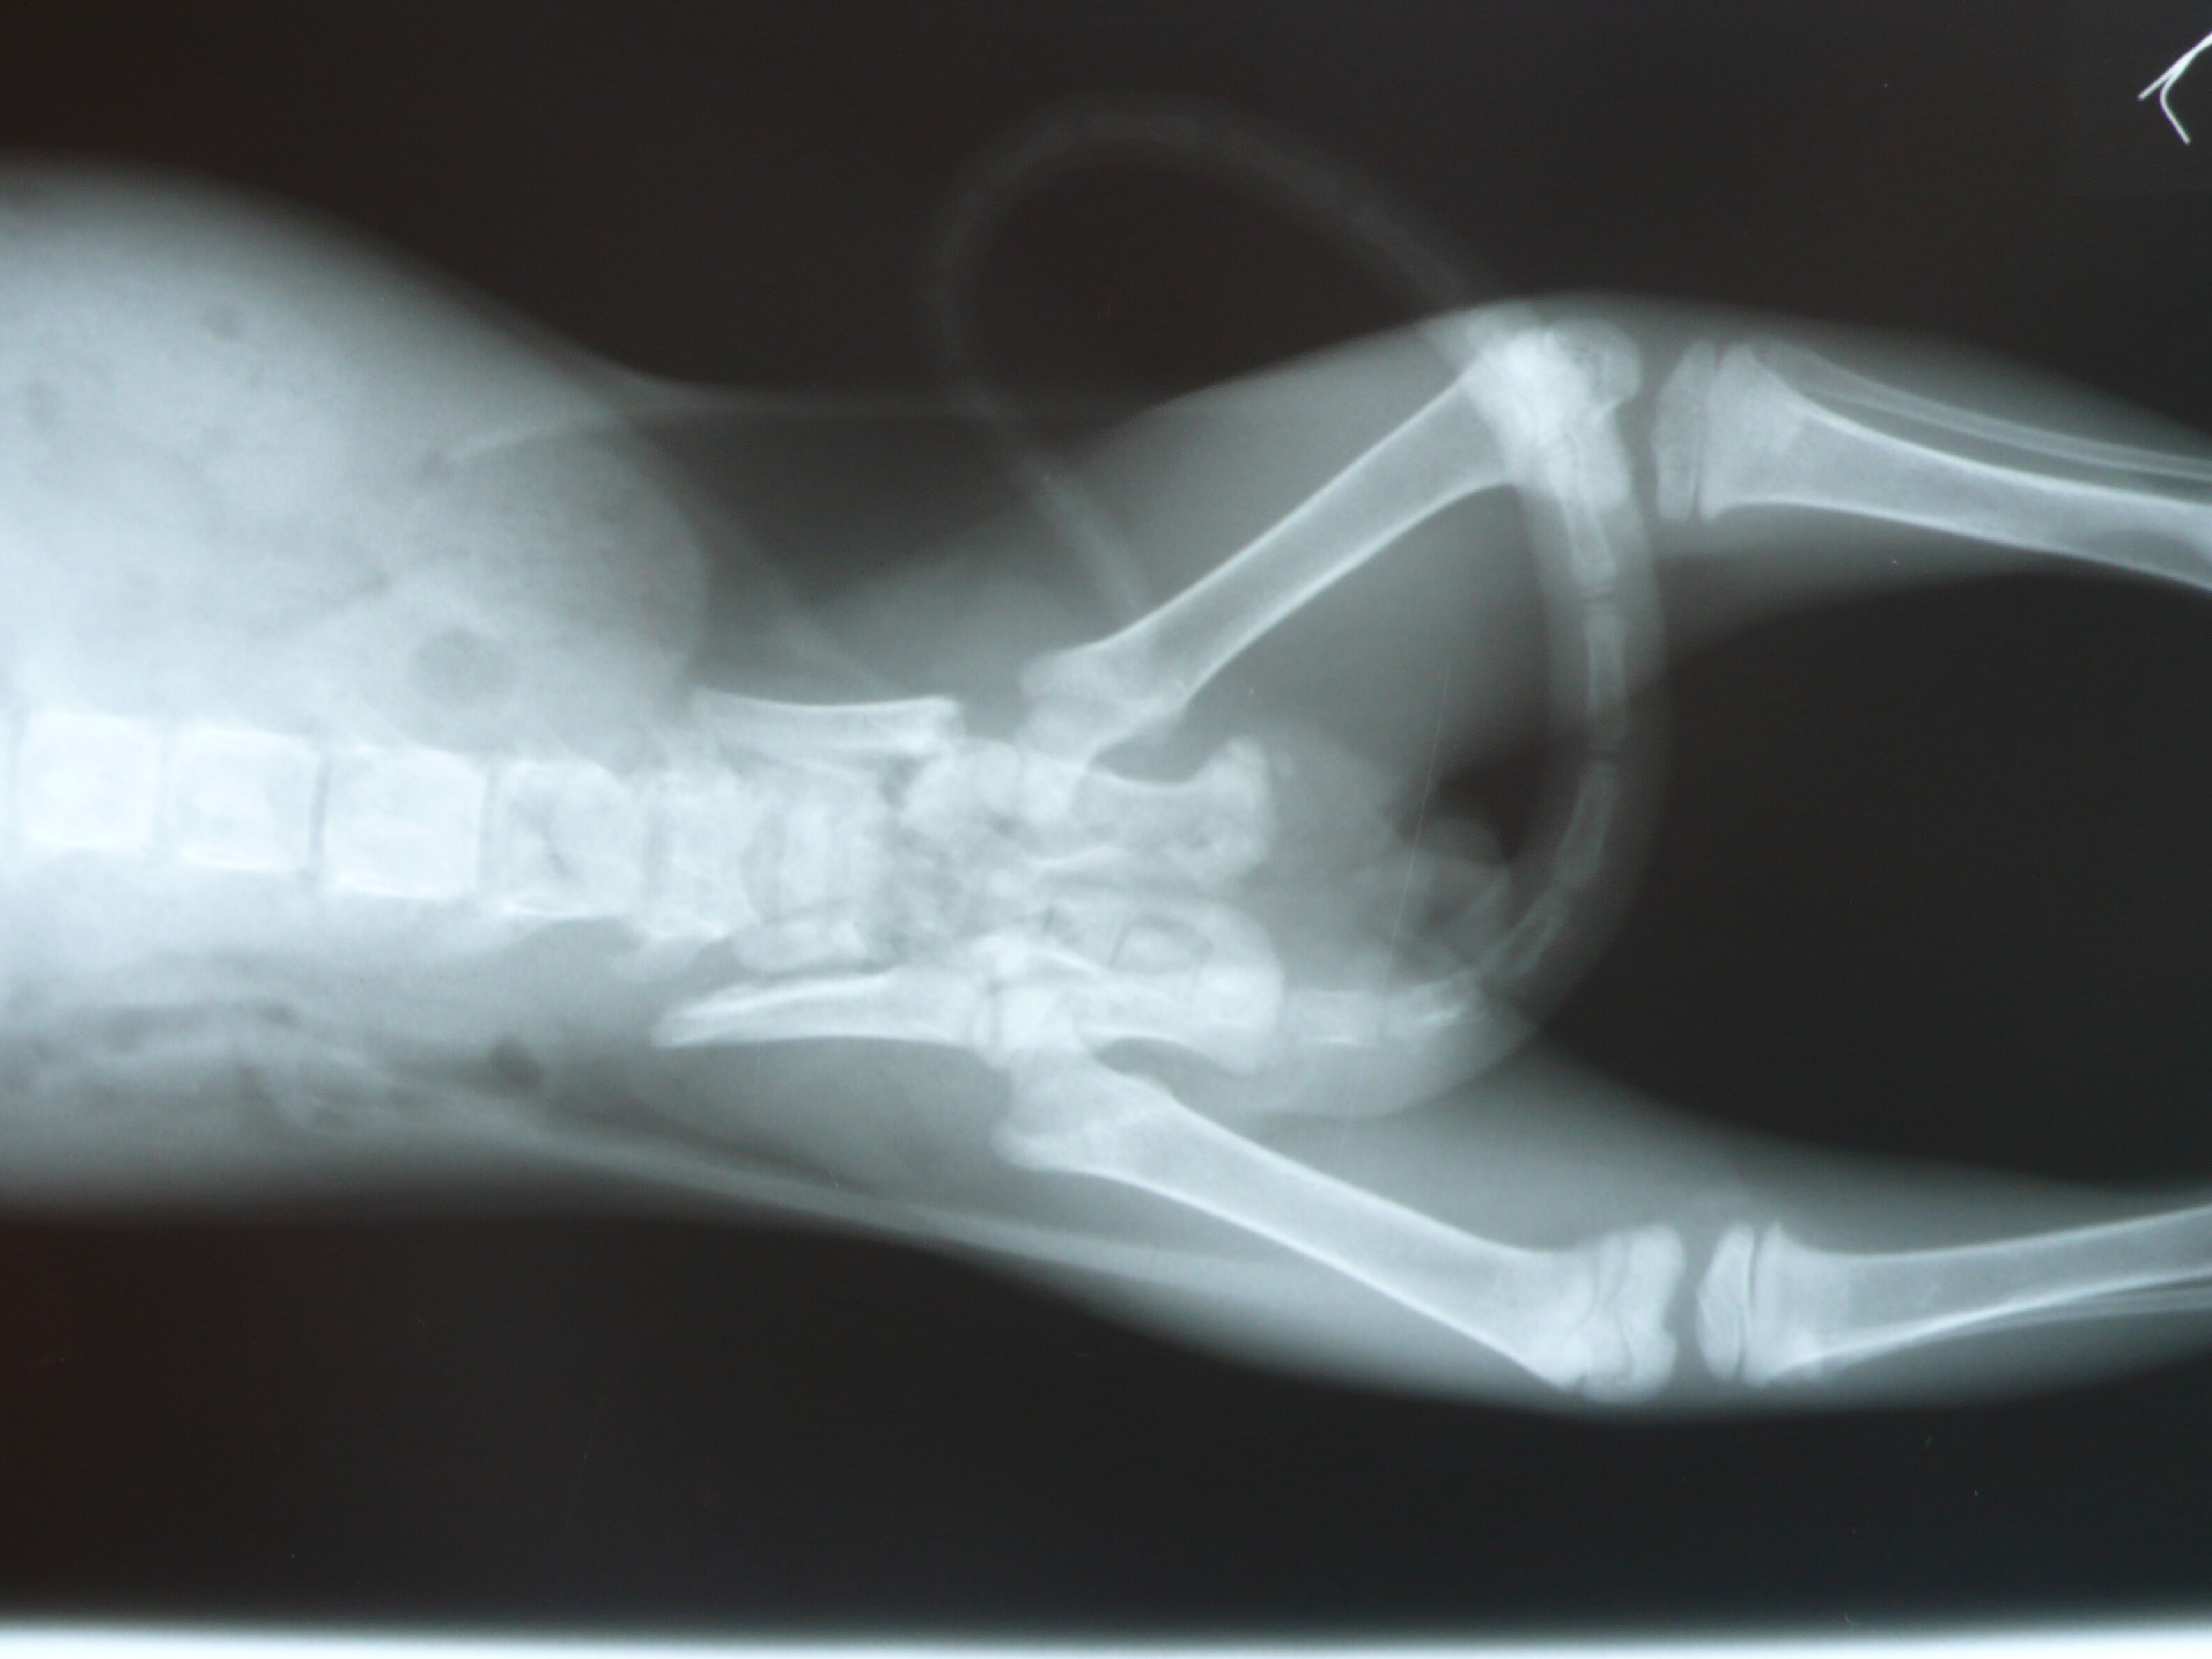

主題: 大同區大龍街骨盤骨折手術小橘白(手手) 申請者姓名: Akimasa Tu 花色: 申請日期: 2012-12-12 00:10:20 申請者部落格: 申請者臉書網址: https://www.facebook.com/akimasa.tu 所在縣市/合作醫院: 台北市/長沁動物醫院 治療費用: 38160元 需求人數: 40人 已結案 (2013-08-06 13:46:45) 報名人員: Hegel Tsai(已付款)、Annabel Wong(已付款)、Ivana Wang(已付款)、火鳳貍(已付款)、Bubujojo(已付款)、Joyce Lien(已付款)、謝佩芳(已付款)、Vincent Ho(已付款)、orangekitten、vanessa(已付款)、wei(已付款)、賴育辰、Minnie Lu(已付款)、劉小蕎、AMY(已付款)、芒果舜(已付款)、Mia Jheng(已付款)、Pa Ssion(已付款)、Pettie Chang、Moon Cat(已付款)、Candice Chao(已付款)、tombosan(已付款)、hungers(已付款)、楊挨打(已付款)、楊挨打、Hugo(已付款)、Jotaro Lin(已付款)、Alison Lee(已付款)、zoechengtw(已付款)、Katrina Chen(已付款)、Emma Chu(已付款)、不不熊(已付款)、Alumi Lu(已付款)、Joyce Hsu(已付款)、以四面佛名義迴向阿咪丶咪仔(已付款)、以四面佛名義迴向阿咪、咪仔(已付款)、Joyce Hsu(已付款)、以四面佛名義迴向阿咪丶咪仔(已付款)、以四面佛名義迴向阿咪丶咪仔(已付款)、以四面佛名義迴向阿咪丶咪仔(已付款)、陳大熊、Miss.Au(已付款)、Fan Chang x3(已付款)、Shirley Tsai(已付款)、 候補人員: 動物病情說明: 這隻小貓是在大龍街一間二手店外面,被一位在當地上班的志工發現,

似乎也無法自行排便,每次都蹲很久大不出來,照X光後才發現,這小

貓有嚴重的骨盤腔骨折,且已經開始癒合,導致無法順利排便,只能每

天用手擠出,且大便形狀是呈凹字形一整條狀,骨盤腔變形非常嚴重!